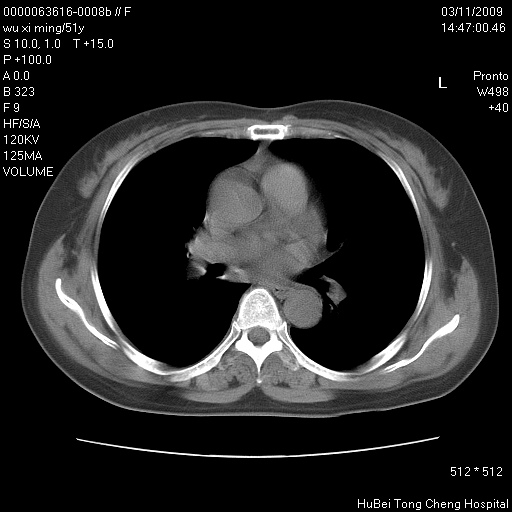

患者 女,51岁。因“胆囊炎,胆囊结石”,行常规术前胸部x线检查发现:右上肺结节病灶,建议行进一步检查。患者无咳嗽、咳痰及咯血等呼吸道症状,近期出现背部疼痛不适。

胸部ct轴位平扫(层厚10mm,螺距1.5,重建间隔10mm;部分层面:层厚3mm,螺距1.0,重建间隔3mm),图像如下:

考虑右肺癌肺内转移!

右肺周围型肺癌伴肺内转移信胸椎转移

右肺周围型肺癌伴肺内转移及胸椎转移。已无手术机会。